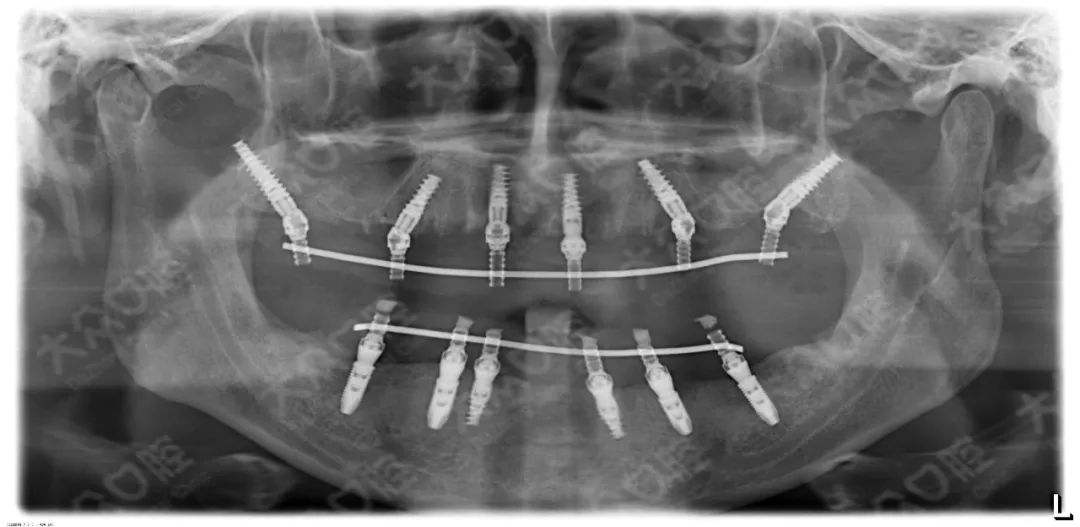

3、种植修复

适用于:各种多颗牙、半口牙甚至全口牙齿的缺失。

优 点:恢复咀嚼功能*多的修复方式,属于固定修复,不能自行取下。

缺 点:费用较高,修复周期较长,有些还需要植骨。修复周期从拔牙算起得半年以上的时间。